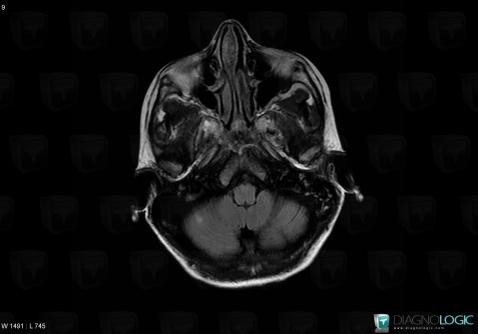

Toxoplasmosis, Posterior fossa, MRI

Here is the specific information in the key image above:

- Diagnosis Toxoplasmosis (link to Abscess), Location(s) Posterior fossa, with gamuts Infratentorial T2W or FLAIR hyperintense lesion